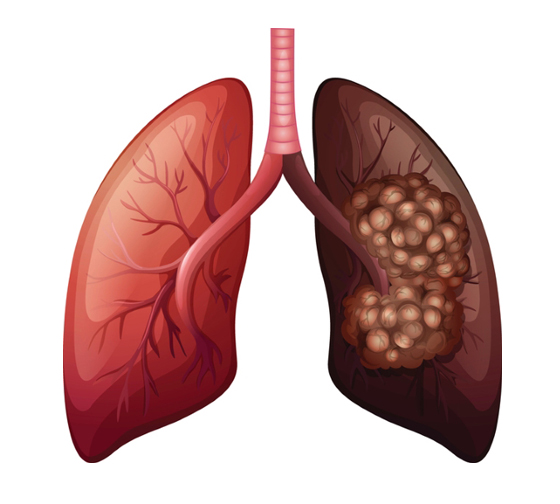

흡연은 폐암의 주요 원인으로 폐암 발생의 약 85%를 차지합니다. 폐암 발병 위험은 흡연한 담배의 개수와 흡연 기간에 따라 달라집니다. 담배를 끊은 사람은 폐암 발병 위험이 낮아지지만, 과거 흡연자는 담배를 피운 적이 없는 사람에 비해 위험이 계속 증가합니다.

흡연 외에도 대기 오염, 마리화나 사용, 담배 연기 및 간접흡연, 난방을 위한 화기 사용으로 인해 석면, 방사선, 라돈, 비소, 크롬산염 등 폐암의 알려진 위험 요인에 노출될 수 있습니다. 폐암, 특히 선암과 기관지 폐포 세포암은 결핵과 같은 다른 폐 질환으로 인한 폐의 흉터로 인해 발생하는 경우도 적지 않습니다.